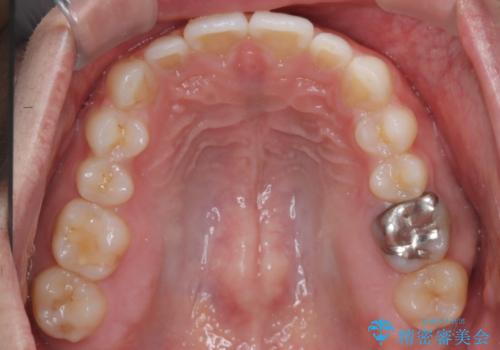

【前突症例】前歯を下げたい

- 前歯の隙間と口元を主訴に来院されました。

インビザラインにて治療を行いきれいな歯並びをつくることができました。

奥歯の噛み合わせもきちんと仕上げることができました。